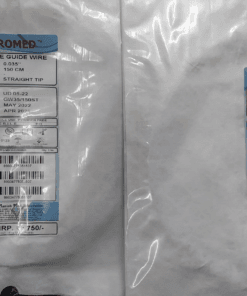

PTFE Guide Wire Set of 10 Urology Size 0.035 Length 150cm Straight

PTFE Guide Wire Set of 10 Urology Size 0.035 Length 150cm Straight

Guide wire with and without PTFE coating

- This wire is made by Galvanized Stainless Steel, and having fixed core. UROMED guide wire has excellent flexibility.

- Size: 0.035”

- Lengths: 150cm

Images are for illustration only. Company may change item design and packaging from time to time. We will ship latest stock available.